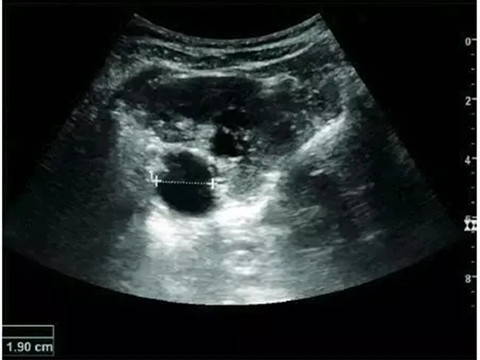

Renal Cyst

Most renal cysts are simple renal cysts that are round in shape and filled with fluid. The incidence of simple renal cysts in people over 50 years old is ≥50%. It is a benign lesion and no further evaluation is required.

Adult simple cyst, dashed distance: kidney length

Features of complex renal cysts: septation, calcification, and irregular thickening of the cyst wall. Doppler ultrasonography is feasible for further evaluation. Bosniak grading and follow-up of complex renal cysts can be performed with contrast-enhanced ultrasonography or enhanced CT. The Bosniak classification can be divided into grades I-IV, grade I: simple cyst, grade IV: cystic malignancy risk 85%–100%.